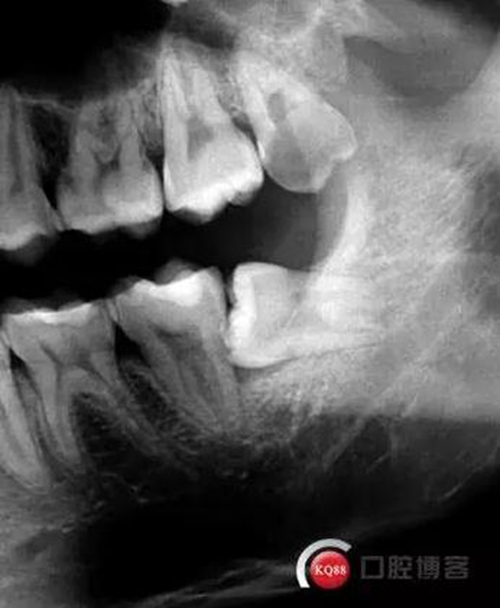

檢查:口內(nèi)可見(jiàn)38未完全萌出,無(wú)松動(dòng),周?chē)例l顏色正常,叩診(—)觸診(—),X線(xiàn)顯示近中阻生,雙根

處理:治療計(jì)劃及費(fèi)用已說(shuō)明,知情同意后,排除拔牙禁忌癥:口腔黏膜消毒,左下頜阻滯麻醉成功后,切開(kāi)翻瓣,渦輪機(jī)去除近中阻力,向近中挺出患牙,拼對(duì)牙體完整,清創(chuàng),置明膠海綿,縫合傷口,咬棉球壓迫止血